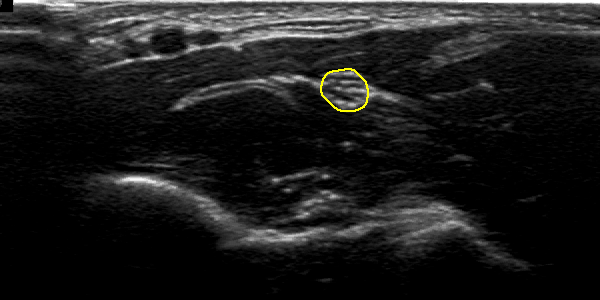

Figure 2 illustrates and example of results in two US images from two different patients. Figures 2 (b) and (e) shows the localisation obtained with CNN and spatiotemporal consistency. The nerve segmentation by PGVF is depicted in figures 2 (c) and (f). One can observe that the automatic segmentation is very close to the one obtained form human experts figures 2 (a) and (d).

Fig. 2: An example of the obtained using deep learning with spatio temporal consistency. Images show the median nerve of two different patients. Left column (a) and (d), each image is the ground truth of the median nerve of each patient. The middle column (b) and (e), represents the localisation result using CNN and spatiotemporal constraint. Right column (c) and (f), shows the segmentation result using PGVF algorithm